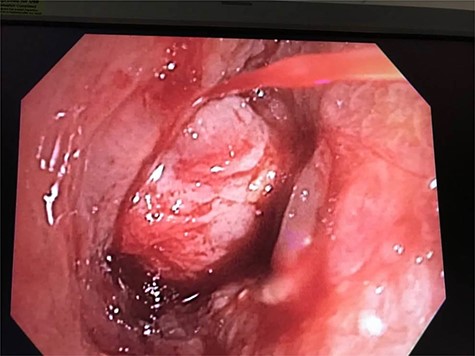

Repeat bronchoscopy was done to evaluate the hemoptysis etiology. After carefully removing residual clot on the right side, an endobronchial mass was seen in the distal bronchus intermedius, which was suspicious for a tumor (Fig. 3). During an attempted biopsy, the patient suffered an episode massive hemoptysis. The patient required transfusion of four units of PRBC’s and vasopressor support.

Bronchoscopic view of distal bronchus intermedius with surrounding inflammation and structure deceptive for endobronchial mass.